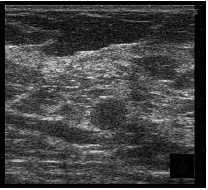

Se prepara la piel con anestesia local (lidocaína 1%) y para la punción ecodirigida del radiotrazador se utiliza una aguja espinal de calibre de 22 G. El radiotrazador nos lo aporta el Servicio de Medicina Nuclear y se trata del 99mtecnecio-coloide de albúmina (Nanocoll®, Amershan Health). La dosis es de 0,8-2 mCi diluidos en suero salino, lo que supone un volumen a inyectar de entre 0,3 a 1 ml. El radiotrazador se inyecta con control ecográfico en la periferia de la lesión con lo que, no sólo se localiza ésta, sino que se permite la migración del mismo hasta el ganglio centinela. Durante la inyección se comprueba cómo se produce un cambio de la ecogenicidad en el extremo de la aguja (fig. 1).

Fig. 1.--Nódulo hipoecoico visible en la ecografía (A). Durante la inyección del radiotrazador se produce un cambio de la ecogenicidad en el extremo de la aguja (B).